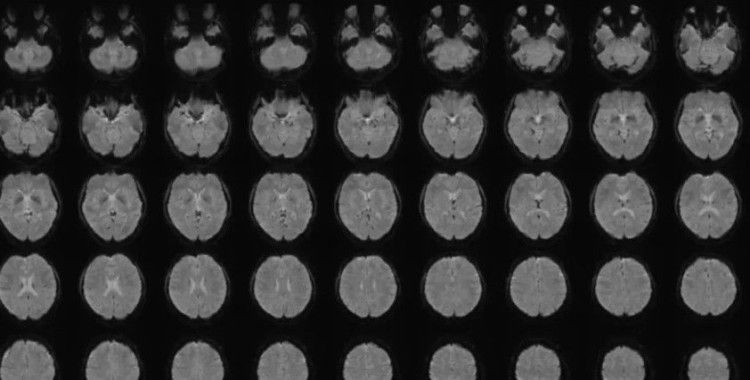

Araştırmada 22-37 yaşları arasındaki 6 Japon katılımcının beyin aktiviteleri, 2180 sessiz video klip izlerken tarandı. Büyük dil modelleri (LLM), videolara ait altyazıları sayısal dizilere dönüştürdü ve ardından “çözücüler” (decoders) olarak adlandırılan yapay zekâ modelleri, beyin aktiviteleri ile bu dizileri eşleyecek şekilde eğitildi.